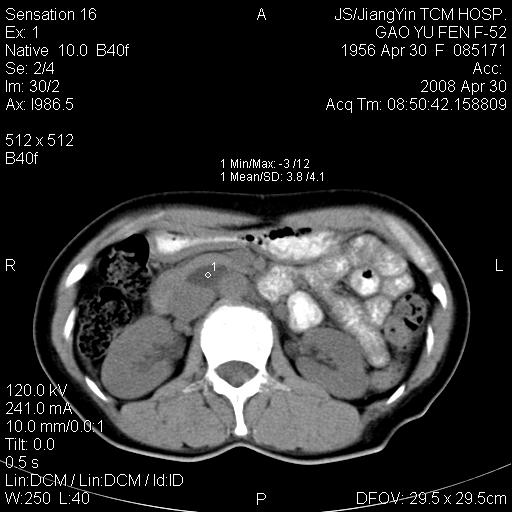

标题: CT13307:肠系膜囊肿? [打印本页]

标题: CT13307:肠系膜囊肿?

积液?囊肿?脂肪瘤?

图像少,不能连续起来看,不太敢确定囊肿前方的条状结构是十二指肠水平段?如果是,那肠系膜囊肿,淋巴管瘤都有可能。

病变位于肾静脉后方,支持腹膜后占位性病变,以囊性淋巴管瘤可能性大.